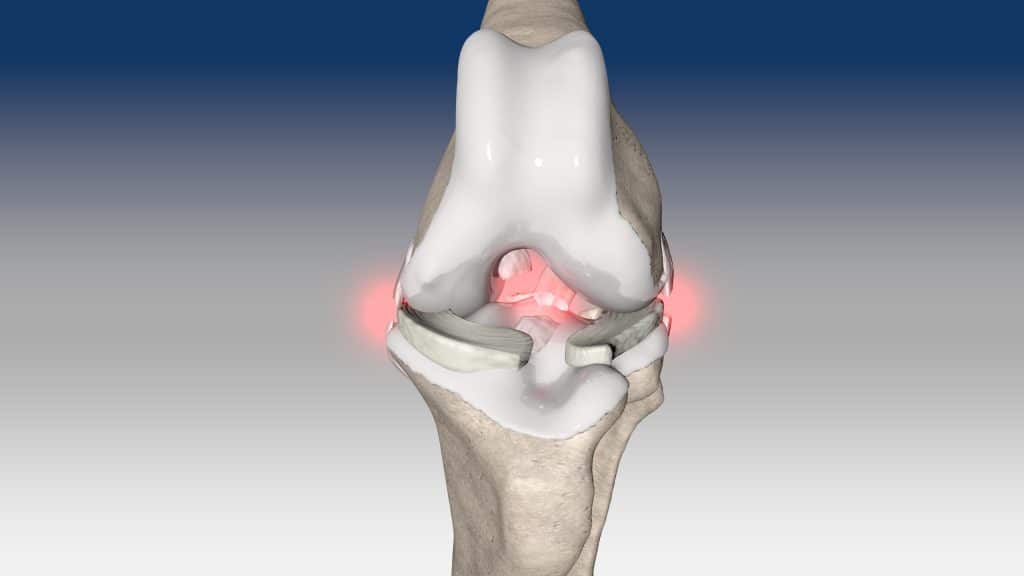

NOVALIG® je syntetický vaz, který lze použít k rekonstrukci vazů a rychlému obnovení jejich fyziologických funkcí.

V případě zkřížených vazů umožňuje intraartikulární rekonstrukci v izometrických bodech připojení, čímž obnovuje biomechaniku kolene a všechny funkce natrženého vazu.

V případě více vazů kolene (kraniální, kaudální, kolaterální) je možné pomocí NOVALIG® anatomicky rekonstruovat každý vaz.